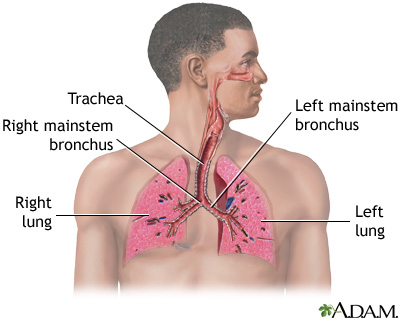

Pulmonary aspergilloma is a mass caused by an infection by the fungus aspergillus. It usually grows in preexisting lung cavities. The infection can also appear in the brain, kidney, or other organs.

Aspergillosis is an infection caused by the fungus aspergillus. Aspergillomas are formed when the fungus grows in a clump in a lung cavity. The cavity is often created by a previous condition. Cavities in the lung may be caused by diseases such as: